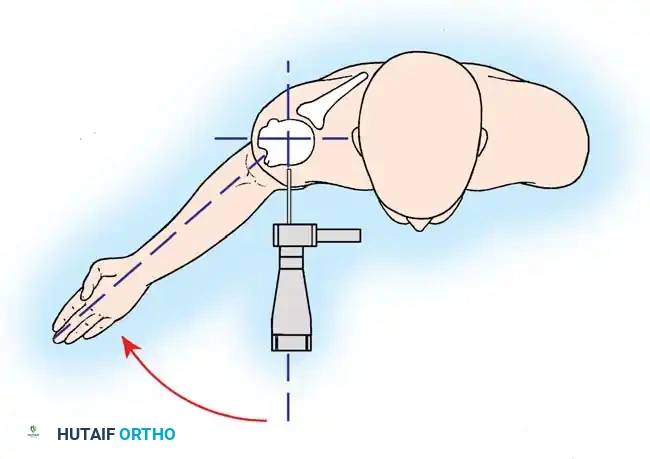

Reverse Total Shoulder Arthroplasty (rTSA)

The rTSA fundamentally alters shoulder biomechanics. By medializing and distalizing the center of rotation, it increases the deltoid moment arm and recruits more anterior and posterior deltoid fibers for elevation, bypassing the need for a functional rotator cuff.

Surgical Nuances for rTSA:

* Glenoid Baseplate: Must be positioned inferiorly on the glenoid to avoid scapular notching. A slight inferior tilt (10 degrees) is often utilized.

* Glenosphere: Typically 36 mm or 42 mm. Larger spheres increase stability and range of motion but may increase the risk of notching.

* Humeral Stem: Often placed in 0 to 20 degrees of retroversion.

Clinical Pearl: Tensioning is the most critical step in rTSA. The joint should be stable in all planes. If the joint dislocates easily, a thicker polyethylene insert or a larger glenosphere is required. However, over-tensioning can lead to acromial stress fractures or brachial plexopathy.